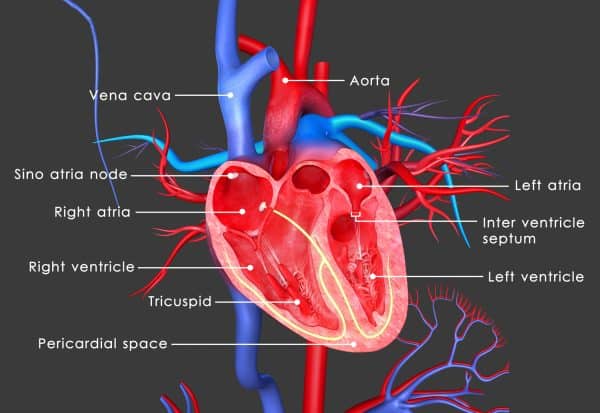

Ο Καθηγητής Καρδιολογίας της Ιατρικής Σχολής του Εθνικού και Καποδιστριακού Πανεπιστημίου Αθηνών, Κωνσταντίνος Γκατζούλης αναφέρει ότι όσον αφορά την καρδιά, μια σειρά δυσμενών επιπτώσεων παρατηρήθηκαν στα αγγεία, στο μυοκάρδιο και στο ηλεκτρικό σύστημα αυτής, οδηγώντας σε οξύ έμφραγμα, προχωρημένη καρδιακή ανεπάρκεια ακόμα και αιφνίδιο καρδιακό θάνατο.